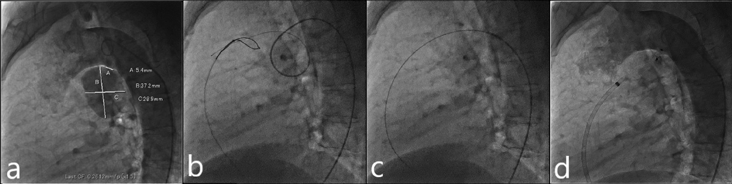

入院翌日に経皮的動脈管閉鎖術を施行した.局所麻酔後,右大腿静脈に6 Fr 11 cm sheath(Medikit Inc., Tokyo),右大腿動脈に5 Fr 11 cm sheath(Medikit Inc., Tokyo)を留置した.カテーテル検査の結果Qp/Qsは1.05,肺血管抵抗係数は0.57 Wood unit·m2.大動脈造影でDAAが造影され,瘤入口部径は5.4 mm,瘤最大径は28.9×37.2 mm,瘤流出部径は2.2 mmであった(Fig. 3a).5 Frジャドキンス型右冠動脈用(JR)カテーテル(Hanaco Medical, Saitama, Japan)を逆行性に進めて瘤入口部にかけて,そこから0.035̋Radifocus guidewire 260 cm(Terumo Inc., Tokyo)を瘤内へ進めて,1ループさせて主肺動脈まで進めた.続いて,順行性に進めて主肺動脈に留置した6 Fr wedge pressure catheter(Gadelius Medical, Kanagawa, Japan)から15 mm径の6 Fr Amplatz goose neck snare (Medtronic plc., Ireland)を進めて,Radifocus guidewire先端を把持して(Fig. 3b)右大腿静脈のsheath外まで引き出した.瘤内のループを伸ばして,大腿静脈–DAA–大腿動脈のwire loopを作成した(Fig. 3c).DAAの大動脈側入口部径が5.4 mmであったため,ADO 12 mm/10 mm(Abbott Structural Heart, Plymouth, MN, USA)を同部に留置した:右大腿静脈のsheathを抜去し,7 Fr Amplatzer™ TorqVue 180 (Abott, Pylmouth, MN, USA)を下行大動脈まで進めた.ADOのRetention skirtを展開して瘤入口部にかけて,デバイスボディを瘤内に展開した.留置後の大動脈造影では閉鎖栓突出による大動脈の狭窄はなく,遺残短絡はごく少量であった(Fig. 3d).特に合併症は認めず,治療翌日からアスピリン100 mgの内服を開始し,退院した.治療後の経過は良好で,術後1カ月の心臓超音波検査で遺残短絡は消失し,術後3カ月の胸部造影CT像で瘤内はほぼ血栓化していた(Fig. 4).

Pediatric Cardiology and Cardiac Surgery 41(2): 84-88 (2025)

Fig. 3 Percutaneous closure of a DAA

a: DAA size: Ao side, 5.6 mm; PA side, 2.2 mm; and maximum diameter, 37.2×28.9 mm. b: The distal end of the Radifocus guidewire is snared in the MPA. c: The Radifocus guidewire is withdrawn into the 6 Fr right femoral sheath to form a wire loop. d: After device deployment, aortic angiography shows no residual leakage from the DAA. DAA, ductus arteriosus aneurysm; MPA, main pulmonary artery.